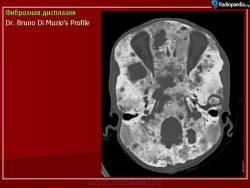

Локализация: для монооссальной фиброзной дисплазии характерно поражение одной из костей лицевого черепа, а также бедренной или большеберцовой кости, реже одного ребра; при полиоссальной фиброзной дисплазии страдают в первую очередь бедренная, большеберцовая и тазовые кости, не исключено и поражение мелких костей стопы, черепа, реже ребер. Рентгенологическая картина фиброзной дисплазии разнообразна. Патологические участки могут быть то более плотными, то более прозрачными по сравнению с окружающей костью, иногда имеют вид «матового стекла». Одни очаги четко отграничены зоной склероза, контуры других расплывчатые, что особенно характерно для костей черепа. Нередко выявляются узуры в кортикальном слое, а при наличии перелома — отчетливая периостальная реакция. При макроскопическом исследовании определяются беловато-красные опухолевые очаги разной плотности, в зависимости от степени выраженности их минерализации. Имеются многочисленные кисты, заполненные желтоватой или красноватой жидкостью, и полупрозрачные участки хряща до 3 см в диаметре.

Для фиброзной остеодисплазии, или болезни Брайцева-Лихтенштейна, характерно нарушение костеобразующей функции мезенхимы, проявляющееся в одной или нескольких костях, что ведет к их деформации и образованию в них очагов разрежения, обычно отграниченных от здоровой ткани кости склеротической каймой. Объем пораженной кости при этом может быть увеличен. Чаще поражаются трубчатые кости, но характерные изменения могут отмечаться и в костях черепа. В таких случаях возможны облитерация придаточных полостей носа, деформация глазниц, сужение отверстий в основании мозгового черепа и в лицевом черепе, ведущее к нарушению функции проходящих через них нервов и сосудов. Заболевание, возможно, наследственное, проявляется с детских лет. Описал в I927 г. отечественный хирург В.Р. Брайцев (1878-1964), несколько позже - американский патологоанатом L. Lichtenstein (1906-1977).